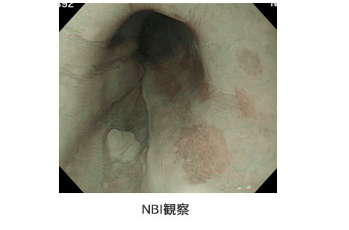

NBI装置(Narrow Band Imaging;狭帯域光観察)付きの内視鏡で検査すると、胃・大腸の表面の血管部分が茶色に見えることによって模様がはっきりします。血管模様によって、通常はまず見えないような小さい病変や、ポリープのタイプが概ねわかるので大変便利で、癌の早期発見に役立ちます。 |